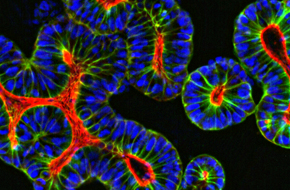

Incorporate the most translatable 3D in vitro models available into your oncology drug development programs with our exclusive Hubrecht Organoid Technology (HUB) licence.

Detect more than 500 different morphological parameters of 3D in vitro models using our powerful high content screening services